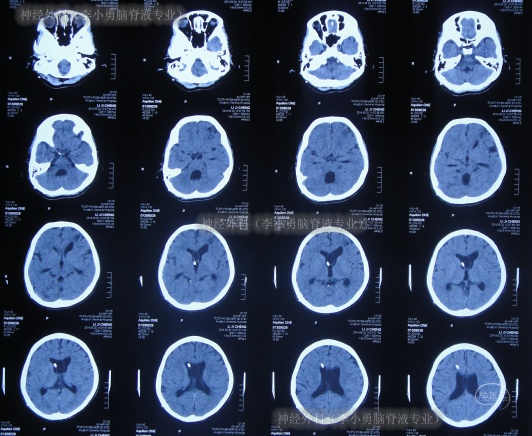

入院次日即2014年8月1日,查头颅CT(图-12)示脑室系统稍扩张(外院拔除脑室外引流后1天)。

图-12:2014年8月1日头颅CT

在术后第4天即2014年8月5日,查头颅CT示脑室较术前稍缩小(图-13)。

图-13:2014年8月5日头颅CT

住院21天即2014年8月20日,查头颅CT(图-14)后按计划进行了左侧侧脑室腹腔分流术。

图-14:2014年8月20日头颅CT